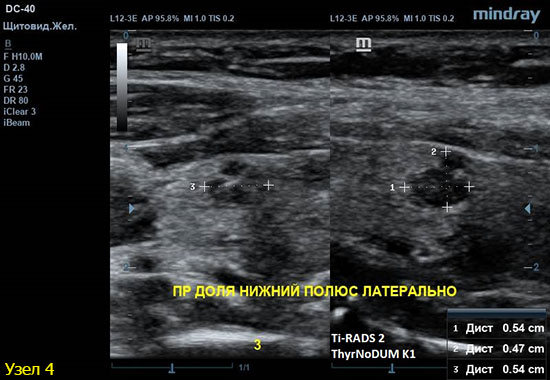

4) Узел правой доли, не прорастает капсулу щитовидной железы (0 баллов), больше широкий чем высокий (0 баллов), не имеет кальцинатов (0 баллов), с ровным четким контуром (0 баллов), изоэхогенный (1 балл), смешанной структуры (кистозно солидный) (1 балл). Количество баллов 2, ACRTi-RADS2, ThyrNoDUMК1. Пункция не показана в связи с низким риском.